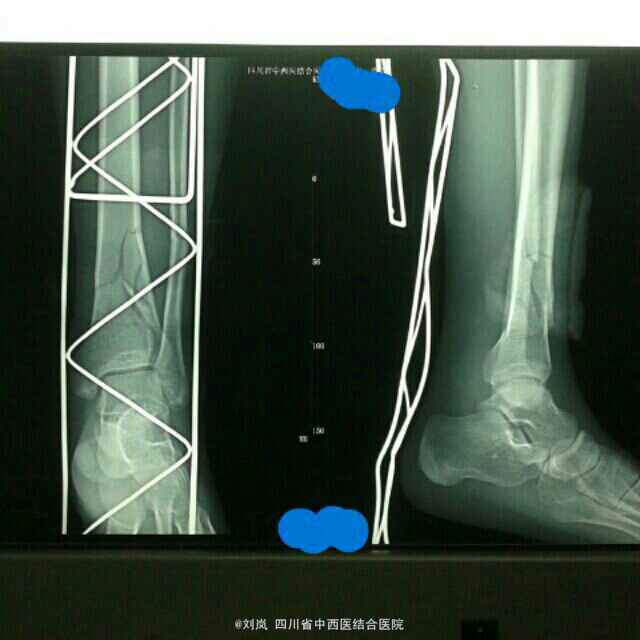

诊断: 1、左胫腓骨下段粉碎性骨折(波及踝关节) 2、营养不良 3、小细胞低色素贫血(原因不明) 4、低蛋白血症 5、脾大 治疗:患者入院后予行"骨折手法整复石膏外固定"制动,复查DR显示:折对位对线良好。向患者及家属说明病情,告知可保守及手术治疗,患者及家属选择手术治疗。故予完善相关术前检查及术前准备,术前输红细胞悬液1.5U及血浆150ml纠正贫血及低蛋白血症,在"全身麻醉"下行了"左胫骨远端骨折闭合复位经皮插入钢板内固定术+左腓骨中下段骨折切开复位钢板螺丝钉内固定术"。术后药物预防感染、消肿、止痛、止血,指导患者行患肢肌力及关节主动功能锻炼等治疗处理。术后2周患肢关节功能活动基本恢复正常,住院3周出院,手术效果理想。

随访:出院后门诊定期复查,术后半年患肢功能活动基本恢复正常,1年后复查,骨折愈合良好,骨折线消失。 讨论:本例骨折保守治疗应该能到达较好的治疗效果,但患者及家属要求手术,根据术前复位后情况,骨折对位对线良好,故选择微创切口治疗,减少创伤及出血。对于胫骨远端骨折内固定钢板选择内侧板还是外侧板?各自优缺点食什么?